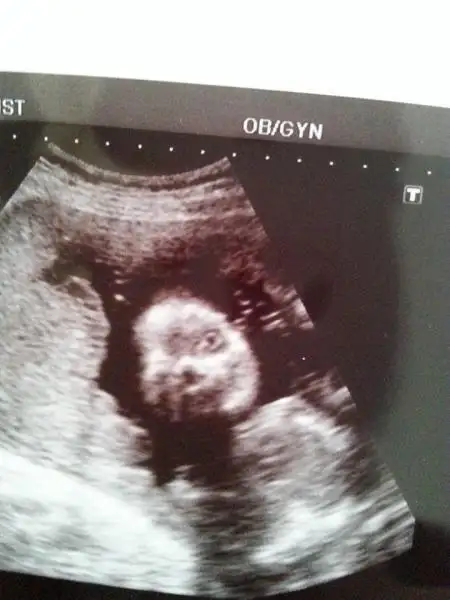

ben altederim onu kendime güveniyom yeter ki babsı ben kızdığımda yüzlemesin yoksa ikisinide sıra dayagına çekerim :9::9::9: yok canım açıktı bir sağa bir sola bakıyodu ki radyologda öyle dedi görüyormusun gözünü sağa sola bakıyo dedi :9::9: benim 2 hafta önce ki randevumda da açıktı gözü eklemiştim buraya bak

Eki Görüntüle 748324

oyyyy gözlere bak anammmm, fıldır fıldır maşallahhhh :nazar::nazar: ben gir çık gir çık foruma kaçırmışım bu resmi, senin kız gözü açık olcek şimdiden belli. kül yutmaz valla:1:

kız senin kız pek uyanık olacak galibaa anaaaaaammmm gözleri şimdiden açılmış ben 27 haftalıkken gittiğimde daha gözleri kapalıydı doktor da bir iki haftaya kadar açılır demişti dee ondan şaşırdım yaniiii:53::53::53::nazar::nazar:

DİDOŞ BAK TAKVİMDE NE YAZIYO BANA Bebeğinizin göz kapakları birleşik olsada, közkapakları kırpma hareketi yapmaktadırlar. GALİBA GERÇEKTEN UYANIK KUZUM :9::9::9: